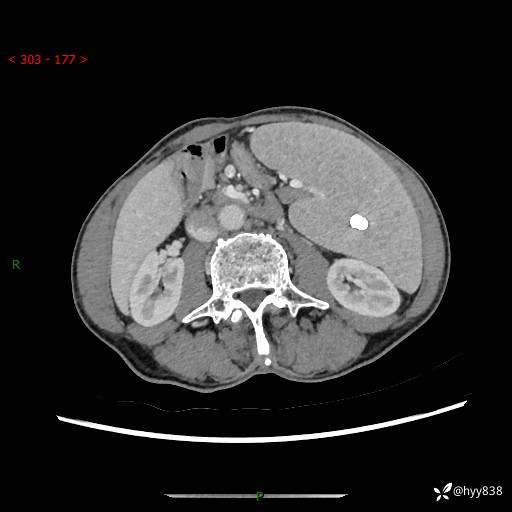

老年男性,脾大并脾脏弥漫粟粒状低密度,淋巴瘤 VS 肉芽肿 VS 血管瘤---结果公布

简要病史: 患者于3月前无明显诱因出现脾大,伴腹部轻微不适,具体不详,无腹痛、腹泻、腹胀,无头晕、头痛、乏力,无恶心、呕吐、呕血,无胸闷、气短、胸痛不适

上腹部CT平扫+增强